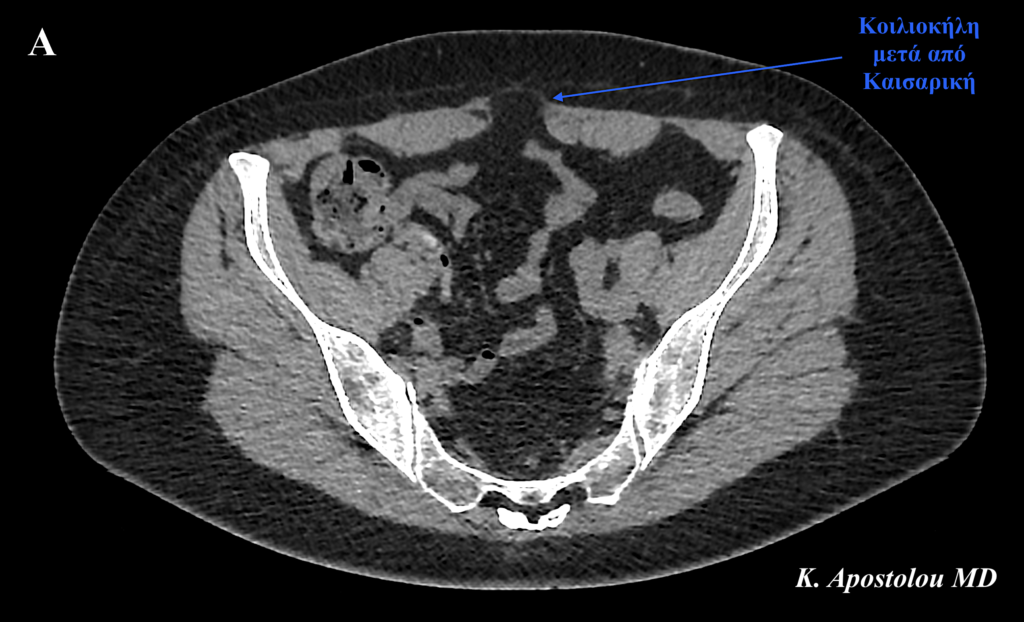

Παρουσιάζουμε την περίπτωση μίας γυναίκας ασθενούς μας ηλικίας 31 ετών, η οποία είχε υποβληθεί σε καισαρική τομή προ 14 μηνών για τη γέννηση του πρώτου της παιδιού.

Η κλινική διάγνωση επιβεβαιώθηκε με την πραγματοποίηση αξονικής τομογραφίας άνω και κάτω κοιλίας, η οποία ανέδειξε την παρουσία μίας κήλης στην καισαρική τομή διαστάσεων 6.5 x 2.5 cm καθώς και μίας σύγχρονης ομφαλοκήλης διαστάσεων 1.9 x 1.4 cm.